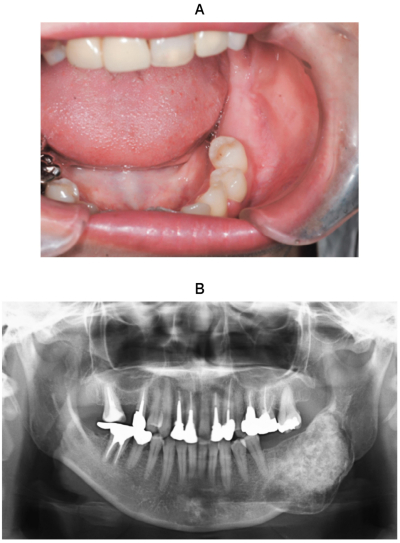

35 歳の女性。下顎左側臼歯部の膨隆を主訴として来院した。病変は骨様硬で、疼痛や下唇の感覚異常はない。初診時の口腔内写真、エックス線画像、CT及び生検時の H-E 染色病理組織像を別に示す。

診断はどれか。1つ選べ。